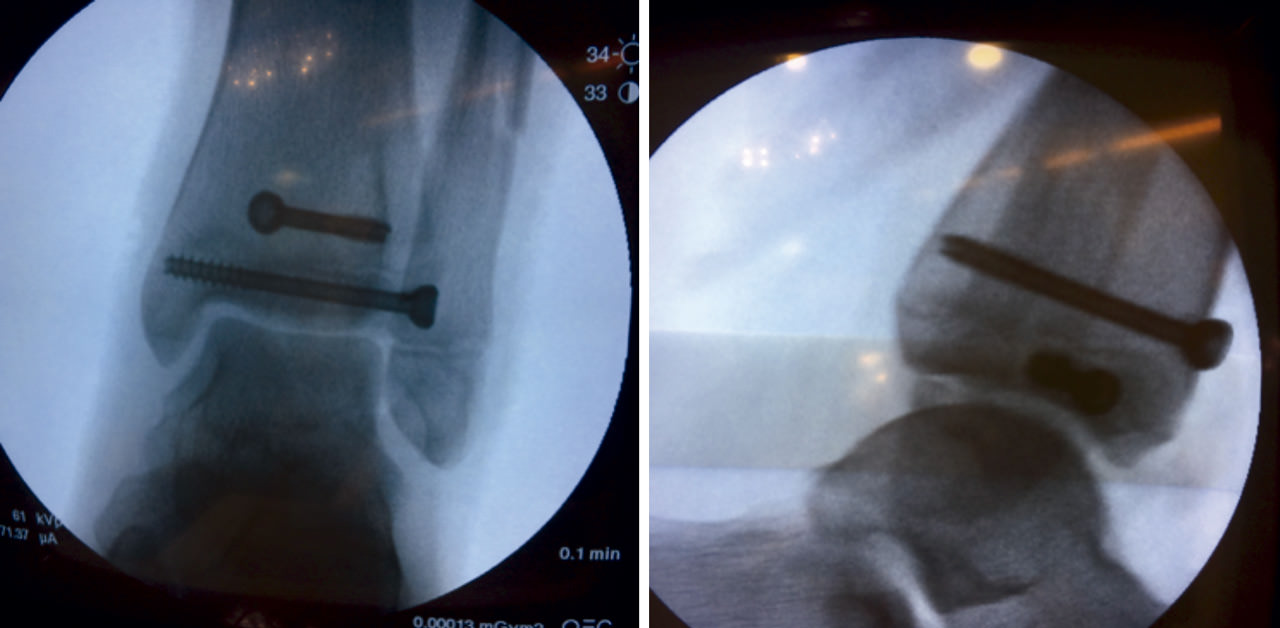

Tras conseguir una adecuada reducción de la fractura, realizamos fijación interna con 2 tornillos canulados de rosca parcial de 16 mm (un tornillo epifisario de lateral a medial y otro metafisario anteroposterior) comprobando bajo fluoroscopio la reducción de la fractura (Figura 5).

Figura 5. Control radiológico intraoperatorio: fijación con tornillos canulados.